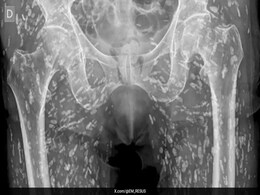

Tapeworm Larvae All News 'Tapeworm Larvae' - 1 News Result(s) Shocking X-ray Reveals Human Body Infested With Tapeworm Larvae Friday January 24, 2025 Science | The condition occurred after the patient consumed undercooked pork, allowing the taenia solium parasite to form larval cysts in soft tissues. www.ndtv.com Share Twitter WhatsApp Facebook Reddit Email 'Tapeworm Larvae' - 1 News Result(s) Shocking X-ray Reveals Human Body Infested With Tapeworm Larvae Friday January 24, 2025 Science | The condition occurred after the patient consumed undercooked pork, allowing the taenia solium parasite to form larval cysts in soft tissues. www.ndtv.com Share Twitter WhatsApp Facebook Reddit Email